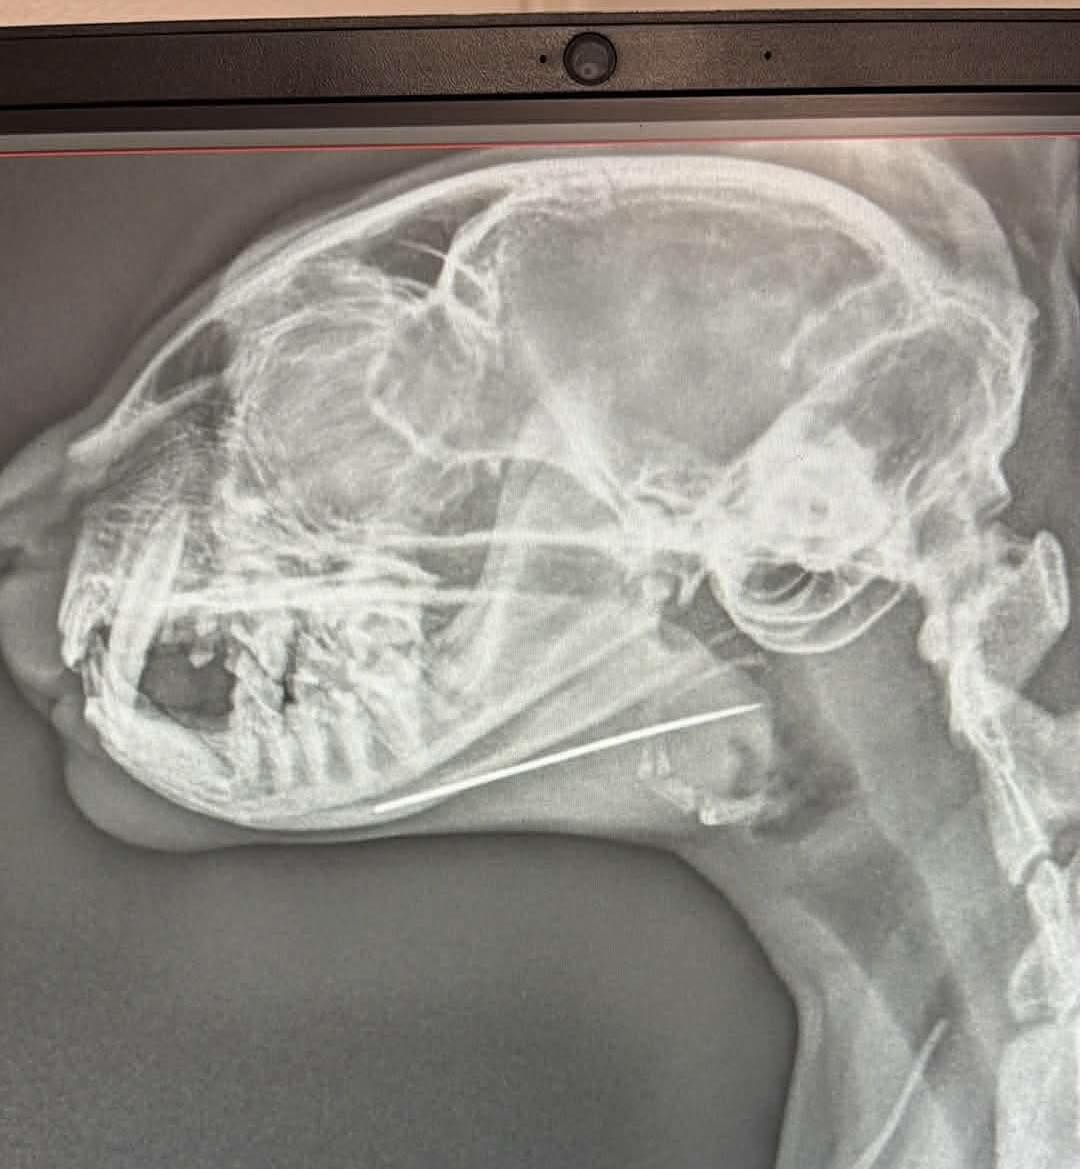

1) mi történt a képen látható cicával?

1) A cica gazdijának szálka ment az ujjába. Ki akarta piszkálni, ehhez keresett egy tűt, ami egy cérnagombolyagba volt beletűzve. A gombolyagot az asztalra tette és kiment megmosni a kezét, de amikor visszatért, a tű már nem volt sehol. Arra gyanakodott, hogy a cica nyelhette le. Először örültünk, mert a röntgennel a hasában nem láttunk semmit. Szerencsére egy másik felvétellel a fejét is megnéztük, és ott már látszott a nyelvébe fúródott varrótű, amit állatorvoshallgató fiammal sikeresen el tudtunk távolítani.